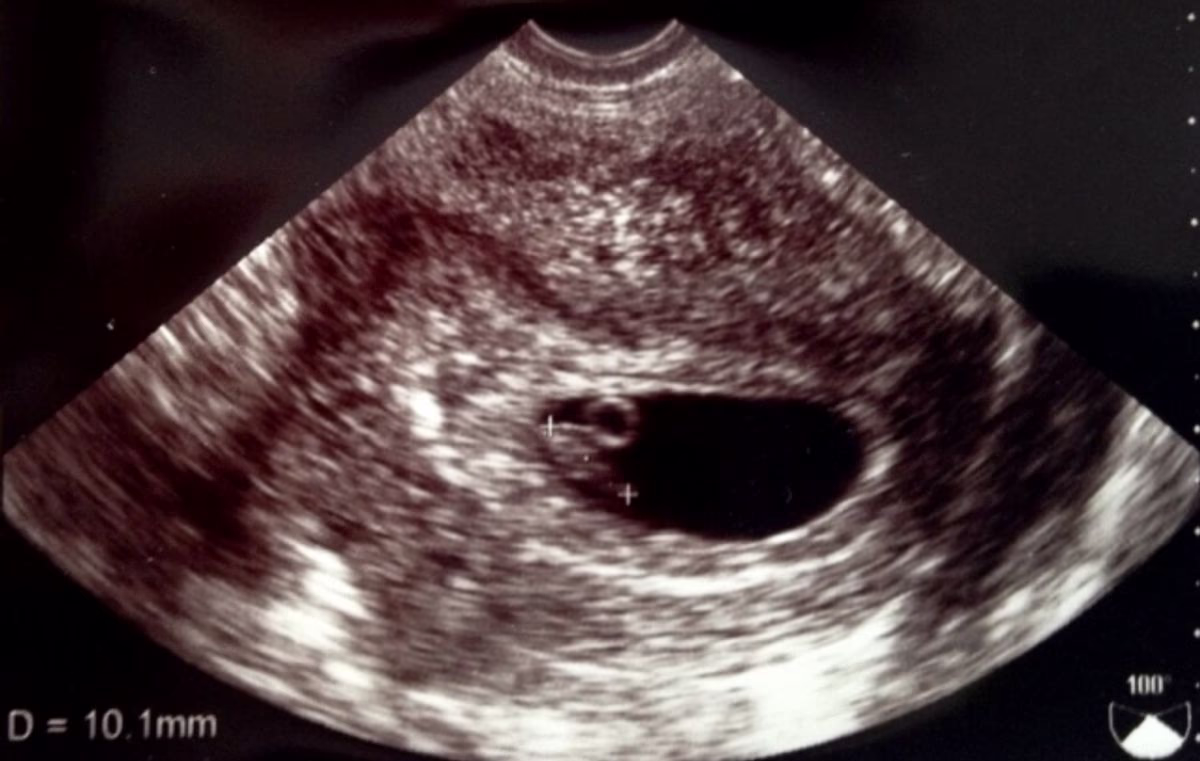

無脳症は、だいたい妊娠11週以降にエコー検査で指摘されます。

エコー検査の他にも、出生前診断のひとつである母体血清マーカー検査でも無脳症の診断が可能です。母体血清マーカー検査は、妊娠15週〜18週に受けることができます。